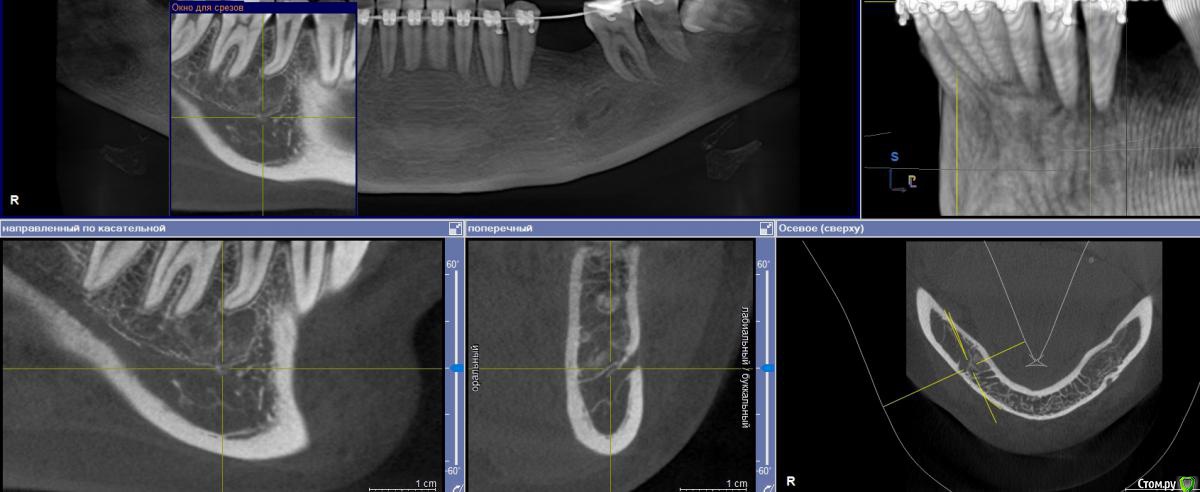

Женька Опубликовано 9 июня, 2020 Поделиться Опубликовано 9 июня, 2020 Тоже спрошу, чтобы не плодить темы.Пришла вот такая пациентка, удаление 28 февраля 2020. Думаю, что ничего страшного и можно ставить не взирая на образование, по крайней мере, мне видится, что это не апексы... тень думаю, потому, что лунка всё еще в стадии заживленияЧто скажете, коллеги? Ссылка на комментарий

Irouil Опубликовано 9 июня, 2020 Поделиться Опубликовано 9 июня, 2020 Как минимум один кусочек чего-то белого на последнем срезе есть Можно ещё прицелку посмотреть. А что с анамнезом? Ссылка на комментарий

Женька Опубликовано 9 июня, 2020 Поделиться Опубликовано 9 июня, 2020 Как минимум один кусочек чего-то белого на последнем срезе есть Можно ещё прицелку посмотреть. А что с анамнезом?В анамнезе у бабушки Cr желудка.Прицела к сожалению нету пломбировочный материал? мне кажется он В остальном считает себя здоровой, по врачам не бегает, на учётах не состоит. Во время удаления (удалял не я) делали прицелы после, и тоже увидели это образование (со слов пациентки). Ссылка на комментарий

Fin Опубликовано 9 июня, 2020 Автор Поделиться Опубликовано 9 июня, 2020 В анамнезе у бабушки Cr желудка.Прицела к сожалению нету пломбировочный материал? мне кажется он В остальном считает себя здоровой, по врачам не бегает, на учётах не состоит. Во время удаления (удалял не я) делали прицелы после, и тоже увидели это образование (со слов пациентки).Удаление 28 было, а когда сделано КТ?. По мне да, лунка в стадии заживления, если вы про дистальное образование то это одонтома, а вот на верхушке гребня что то есть. Думаю что ничего страшного,сделаете прицельный снимок перед имплантацией и если что во время операции уберете. Ссылка на комментарий

red_butler Опубликовано 9 июня, 2020 Поделиться Опубликовано 9 июня, 2020 Что скажете, коллеги? я бы удалил и возможно на гистологию отправил 2 Ссылка на комментарий

Женька Опубликовано 9 июня, 2020 Поделиться Опубликовано 9 июня, 2020 Удаление 28 было, а когда сделано КТ?. По мне да, лунка в стадии заживления, если вы про дистальное образование то это одонтома, а вот на верхушке гребня что то есть. Думаю что ничего страшного,сделаете прицельный снимок перед имплантацией и если что во время операции уберете.Кт от 8 июня. я бы удалил и возможно на гистологию отправилИз-за анамнеза родословной? Ссылка на комментарий

red_butler Опубликовано 9 июня, 2020 Поделиться Опубликовано 9 июня, 2020 Кт от 8 июня. Из-за анамнеза родословной?Нет, новообразование имеет оболочку, не хотелось бы удалять имея там имплант 1 Ссылка на комментарий

Женька Опубликовано 9 июня, 2020 Поделиться Опубликовано 9 июня, 2020 Записал срезы Кт, вижу что-то похожее на корень с ярким материалом в области края гребня. И образование, по плотности как кортика. + лунки заживающие. Ссылка на комментарий

red_butler Опубликовано 9 июня, 2020 Поделиться Опубликовано 9 июня, 2020 https://youtu.be/1pW5wBBAbls Записал срезы Кт, вижу что-то похожее на корень с ярким материалом в области края гребня. И образование, по плотности как кортика. + лунки заживающие.Похоже на корень. А есть снимки до удаления? И настораживает, зачем коллеги делали rg после удаления.., Ссылка на комментарий

Женька Опубликовано 9 июня, 2020 Поделиться Опубликовано 9 июня, 2020 Похоже на корень. На верхушке гребня с ярким рентгеноконтрастным материалом? или где-то в другом месте? А есть снимки до удаления? Была вроде ОПТГ, попробую вытянуть у пациентки.И настораживает, зачем коллеги делали rg после удаления..,Именно из-за этого плотного образования. Ссылка на комментарий

Женька Опубликовано 10 июня, 2020 Поделиться Опубликовано 10 июня, 2020 А есть снимки до удаления? Можно ещё прицелку посмотреть. Прицелки нет, как я сказал, но есть ОПТГ до удаления, правда не лучшего качества... Ссылка на комментарий

Irouil Опубликовано 10 июня, 2020 Поделиться Опубликовано 10 июня, 2020 я бы удалил и возможно на гистологию отправилТут мне кажется верное решение Похоже на какую-то цементому не удалённую, но все же Ссылка на комментарий

Женька Опубликовано 10 июня, 2020 Поделиться Опубликовано 10 июня, 2020 Тут мне кажется верное решение Похоже на какую-то цементому не удалённую, но все жеВозможно меня неправильно поняли) у бабушки пациентки был Cr в анамнезе...Или разницы нет и не стоит имплантировать пока не уберу образование?Но тогда другой вопрос, как оптимальнее его вытащить? или не важно и всё равно придется аугментировать и ждать? Ссылка на комментарий

Irouil Опубликовано 10 июня, 2020 Поделиться Опубликовано 10 июня, 2020 Возможно меня неправильно поняли) у бабушки пациентки был Cr в анамнезе...Или разницы нет и не стоит имплантировать пока не уберу образование?Но тогда другой вопрос, как оптимальнее его вытащить? или не важно и всё равно придется аугментировать и ждать?Про бабушку я понял. Но если эта штука осумкована (а на орто до тоже так кажется), то вокруг импланта пойдёт расти ее капсула, а не кость. По крайней мере есть такой риск. Ну а на гистологию всегда лучше сдать, чем не сдать Ссылка на комментарий